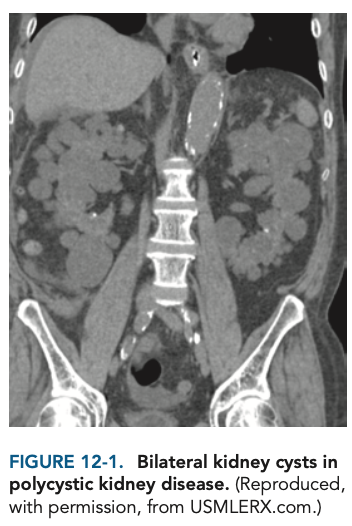

Autosomal dominant polycystic kidney disease (ADPKD). ADPKD has a prevalence of approximately 1:1,000 and is the leading genetic cause of chronic renal failure. It is diagnosed with imaging.

Colonic diverticular disease is the most common extrarenal effect of ADPKD. Hepatic cysts (Figure 12-1) are present in 50%–70% of patients and are generally asymptomatic with little effect on liver function. There is also an association between ADPKD and berry aneurysms of the circle of Willis, which show familial clustering. Rupture of such aneurysms results in subarachnoid hemorrhage and increased mortality and morbidity. Mitral valve prolapse is found in 25% of patients with this disease. Most patients with APDKD die from cardiac causes. Cardiac hypertrophy and coronary disease are extremely common.